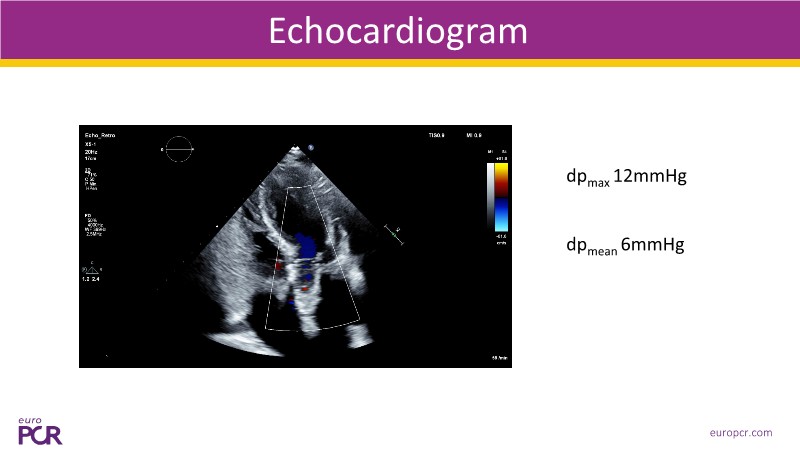

This session explores some of the most clinically complex scenarios encountered in TAVI practice. Three real-world cases address key challenges such as intervention sequencing and transcatheter valve selection in patients with combined coronary artery disease and severe aortic stenosis. The session also examines coronary obstruction risk assessment and protection strategies during redo TAVI, and discusses specific implantation techniques for anatomically complex cases, including large aortic valve anatomy.